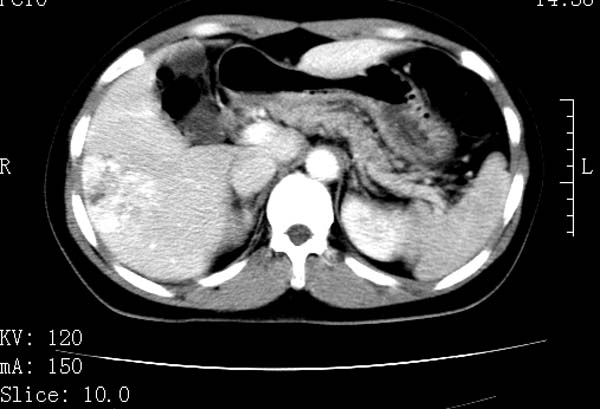

标题: CT22086:女44岁 肝右叶占位增强示巨大血管瘤,门脉期发现小 [打印本页]

标题: CT22086:女44岁 肝右叶占位增强示巨大血管瘤,门脉期发现小

请大家观察一下小灶   发表意见,谢谢

支持肝右叶血管瘤诊断。 小病灶亦考虑血管瘤改变。温习一下:

肝海绵状血管瘤ct平扫常呈均匀低密度,与邻近血管密度相仿。在脂肪肝背景下可呈相对高密度。在增强扫描时,一般早期(动脉期)呈周边结节状或弧形强化,其密度与同层面的血管密度相仿,随着时间延迟向中央渐进性充填,注药后5~7分钟,逐渐扩大至全瘤强化,强化密度逐渐降至稍高于或等于正常肝脏。大的血管瘤往往中央有星形、大的低密度区,可以为纤维化或囊性变所致,纤维化成分可在延迟2 o分钟时完全充填,呈等密度,但囊变区则不会强化。不典型ct表现常见于≤3 cm的小血管瘤。小的血管瘤可以在动脉期即呈全部致密的均匀强化,不呈典型的周边结节状强化表现,但其密度往往较高,与主动脉相仿,在延迟期呈高或等密度。其他不典型的ct表现有:增强扫描强化不明显,呈点状较轻程度的强化,充填慢,可能与供血动脉较细和较大的血管间隙有关以及中央先强化等。

延迟扫描三个病灶都呈等密度改变。肝多发血管瘤,较典型。